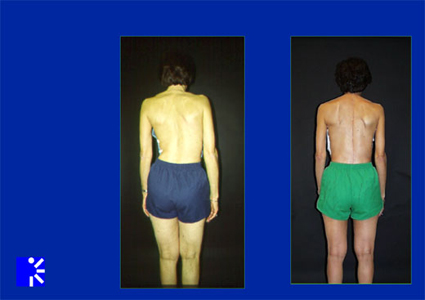

What does it mean when a doctor finishes a schedule of treatment for degenerative scoliosis?

When doctors finish a schedule of treatment for Adult Degenerative Scoliosis, they will try to determine if the patient is feeling or seeing any improvement in their symptoms. These improvements can range from physical pain to cosmetic misalignments and differences.